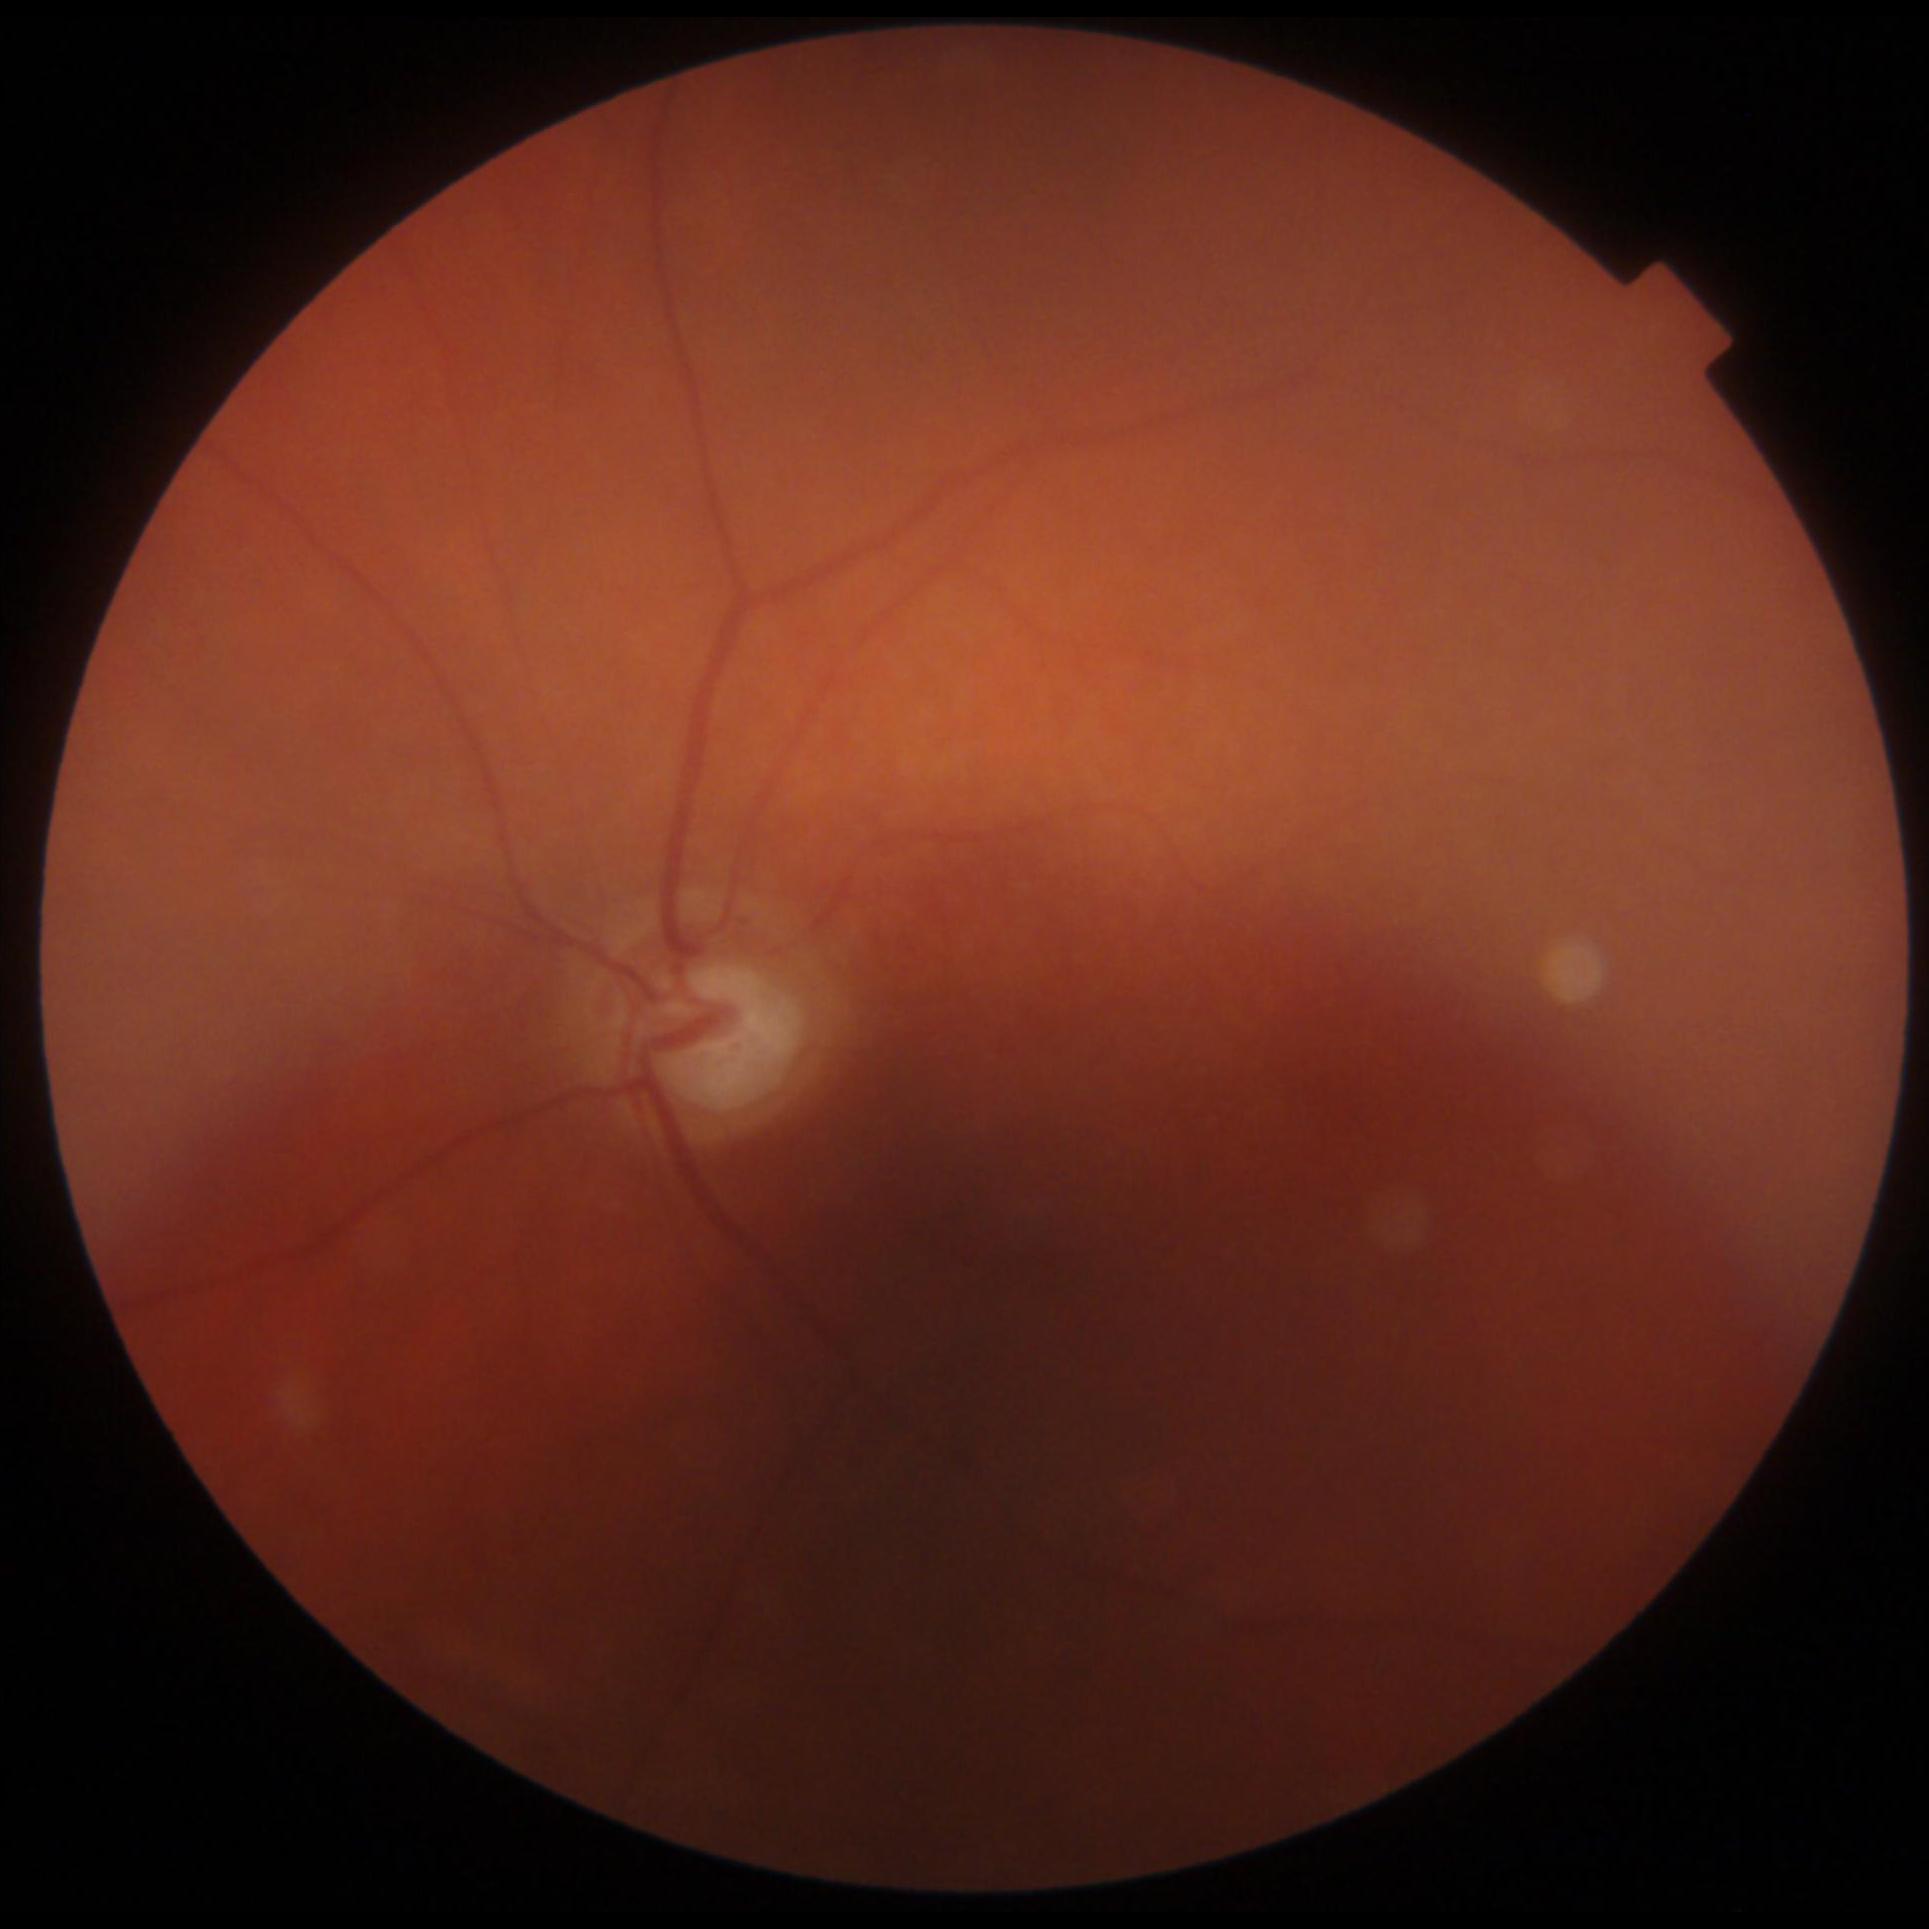

GON is diagnosed through a comprehensive ophthalmic examination that includes intra-ocular pressure (IOP) measurement, anterior chamber and angle assessment, optic disc (OD) inspection, visual field assessment, and optic nerve head imaging [1, 4]. Although effective, these procedures require the expertise of an ophthalmologist and access to specialized, often costly, equipment, which can be a limiting factor. Alternatively, computer-aided analysis of digital fundus images (DFI) can be used to identify GON. DFIs are captured using a fundus camera, which photographs the posterior segment of the eye and provides a clear view of the OD [5].

Images

The dataset consists of 747 DFIs, including:

- 548 glaucomatous DFIs (73%)

- 199 non-glaucomatous DFIs (27%)